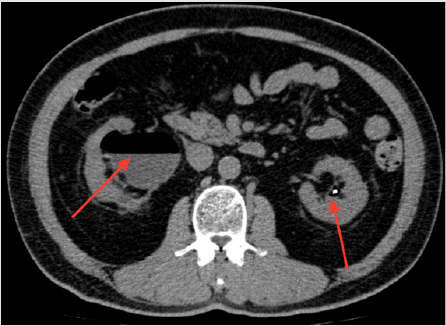

However, the right kidney was still hydronephrotic. Renal functional scan (MAG-3) 12 months post-operative confirmed obstructed right kidney likely at right upper ureter. Right kidney differential function was at 26.9%. Plain CT prior to reconstruction surgery showed gaseous collection in bilateral collection system down to urinary bladder, which was more severe on the right side, and bilateral non-obstructing renal stones but no ureteric stones (Figures 1-3).

Patient was, however, asymptomatic. There were no clinical features suggestive of urosepsis. Physical examination was unremarkable. Since the last endourological procedure Right URSL was performed 18months ago, the possibility of gas collection post-instrumentation is minimal. The clinical diagnosis was asymptomatic emphysematous pyelonephritis. He was then admitted to our urology unit for further management. Urine culture showed Escherichia coli. According to bacteriology, 2-weeks Intravenous Ceftriaxone was commenced. No urinary drainage was performed in view of stable vital signs and asymptomatic condition. Insulin regimen was modified, and his diabetes improved. His antibiotics regimen was stepped down to oral levofloxacin for 2 more weeks. He was discharged after 4 weeks of antibiotics.